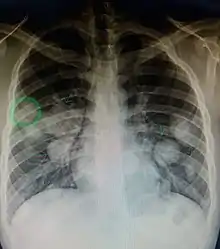

| Illustration showing hematogenous metastasis | |